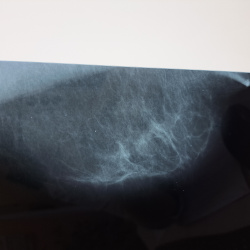

Добрый день. Нужна ваша помощь)Женщина 1964г,жалоб нет ,проф осмотр, маммография 2020г норма. Какую категорию на образование выставить? смущает контур в прямой проекции, но на косой не так всё плохо